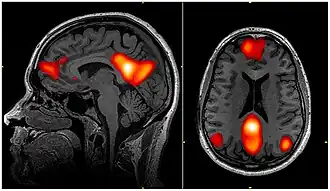

Research indicates that these drugs also influence brain regions such as the default mode network (DMN) (see figure 7), which is related to introspection, self-awareness, self-referential thoughts, and memory, and is usually active when we are not focused on an external task (Millière, 2017; Senanayake, 2022). Furthermore, psychedelics have been shown to decrease DMN activity, potentially contributing to the sensation of ego loss by disrupting regular self-awareness and altering brain connectivity between different regions. DMN decreased activity is also apparent during deep meditation and other experiences of ego dissolution.

Psilocybin works slightly differently as it increases the connection between the DMN and the task positive network (involved in problem solving, decision-making focused attention and executing actions), while also reducing the inverse relationship between these areas during meditation (Senanayake, 2022). Additionally, psilocybin decreases the coupling between the DMN and the medial temporal lobe, which is linked to dream-like states and depersonalisation disorders. This uncoupling results in the usual rigid sense of self and distinctions between the self and the external world becoming less defined, contributing to experiences of ego dissolution or ego death.

A study by Lebedev and colleagues (2015) explored the neural mechanisms behind ego disturbances, particularly ego dissolution, in the context of schizophrenia and psilocybin-induced psychedelic experiences. The research was conducted on 15 healthy participants and measured using functional MRI scans, comparing brain activity after administering a saline placebo or 2 mg of psilocybin. The results suggested that psilocybin-induced ego dissolution is linked to decreased connectivity between the medial temporal lobe and high-level cortical regions, breakdown of the salience network, and reduced interhemispheric communication. Overall, the results imply that the regular functioning of these brain networks is responsible for the sense of self and offer insights into ego disturbances in clinical and non-clinical settings (Lebedev et al., 2015).